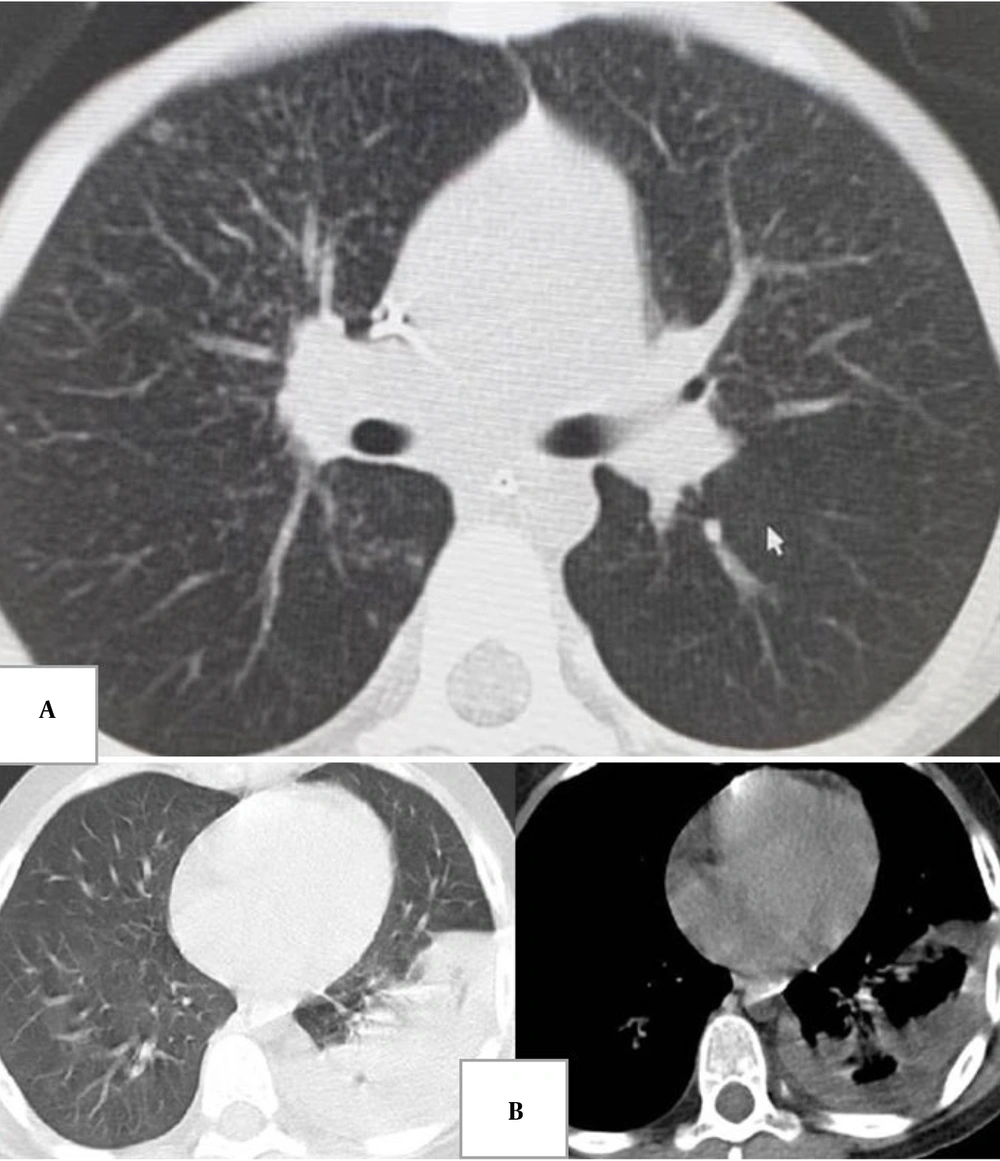

Chest CT is rarely performed in MIS-C and is primarily reserved for specific clinical concerns such as sepsis or suspected pulmonary embolism (40, 46). Limited reports describe CT findings that mirror CXR patterns: Basal consolidation, GGO, interstitial changes, small pleural effusions, lymphadenopathy, and cardiomegaly (40). Rarely, pulmonary nodules have been reported (40, 42).

![A, centrilobular nodules in a 5-year-old boy with abdominal pain [atypical for coronavirus disease 2019 (COVID-19)]; B, segmental consolidation and pleural effusion in an 11-year-old boy with flank pain and cough (atypical for COVID-19). A, centrilobular nodules in a 5-year-old boy with abdominal pain [atypical for coronavirus disease 2019 (COVID-19)]; B, segmental consolidation and pleural effusion in an 11-year-old boy with flank pain and cough (atypical for COVID-19).](https://services.brieflands.com/cdn/serve/31710/72f4fab98e3f54fc099fd868adba87f7bf14a760/apid-14-2-146685-g002-preview.webp)